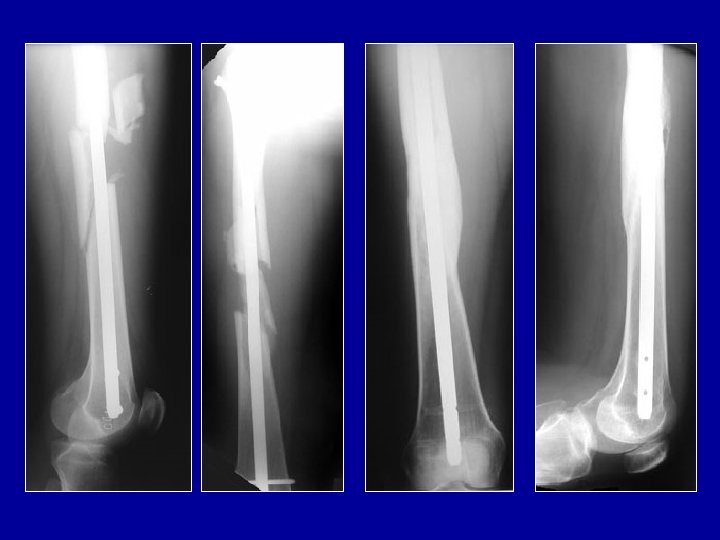

Enclouage du tibia à foyer fermé Clou simple Clou à ailettes Clou verrouillé par vis

Qualité du cal osseux après enclouage du tibia à foyer fermé Avantages de l’enclouage Préservation de l’hématome Pas de dépériostage Cal volumineux

Clou de tibia Verrouillage proximal Verrouillage distal Photo J. Chouteau

Clou à foyer fermé verrouillé Vis enlevées à 3 mois Guérison 6 mois